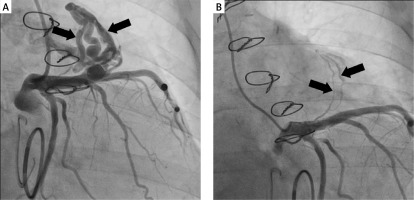

Figure 1

Coronary angiography images of a coronary-pulmonary fistula originating from the LAD to the pulmonary trunk before (A) and after the procedure (B)

The cardiac surgery clinic received a referral for surgical treatment of a complex heart defect in a 74-year-old female patient with heart failure classified as NYHA II/III due to mitral regurgitation and tricuspid regurgitation. The patient also had type II diabetes and persistent atrial fibrillation. Over the past 5 years, the patient had reported a decline in exercise tolerance and intermittent chest pain. During preoperative diagnosis, echocardiography revealed dilatation of the heart cavities, dilatation of the tricuspid and mitral annuluses, along with left ventricular systolic dysfunction. Coronary angiography showed no significant stenosis in the coronary arteries, but it did reveal a coronary-pulmonary fistula originating from the LAD to the pulmonary trunk, which was classified as a hemodynamically significant defect (Figure 1 A). The entire diagnostic and therapeutic process was based on the coronary angiography. Therefore, the use of multislice computed tomography (MSCT) was unnecessary. Mitral valve plication and tricuspid valve plication were performed, with implantation of a 32 mm CE Physio ring for each. Due to the complexity of double-valve surgery, the prolonged duration of the operation and the non-visibility of the fistula outlet, no further action was taken in order to avoid serious post-operative complications. The enlargement of the fistula, chest pain and exertional dyspnea supported the hemodynamic significance of the anomaly. The patient was deemed eligible for an attempt at percutaneous closure of the coronary-pulmonary fistula, which was successful. The procedure was carried out via the left radial artery using a 3.5 6F EBU catheter and a Papyrus 4.5 × 15 stent graft. The stent graft was implanted at a pressure of 16 atm, tightened at 18 atm, and the entire length of the stent was finally balloon inflated to a pressure of 22 atm. Closure of the fistula lumen was achieved, with residual contrast retention visible in the vessel. A small vessel undergoing trace contrast was preserved outside the perimeter of the length of the stent graft (Figure 1 B). There were no complications during the procedure, and the patient was discharged without any complaints. During follow-up coronary angiography, the procedure’s effect was maintained, and the patient was prescribed conservative treatment with acetylsalicylic acid and apixaban for 6 months. After that, due to persistent atrial fibrillation, treatment with apixaban was continued. The use of acetylsalicylic acid was justified by the implantation of a stent graft. There are no algorithms regarding the treatment of rare anomalies such as CAFs and antiplatelet therapy. An individual approach is crucial in each case. Further annual monitoring with MSCT is recommended. Over the course of the 2-year follow-up period, the patient has exhibited neither signs of illness nor cardiovascular complications. Nevertheless, in the event of any coronary-related symptoms, heart failure, or the emergence of a new murmur, follow-up coronary angiography is recommended. Currently, the patient feels well; hence, no such procedure is planned.